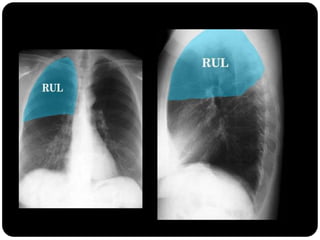

 Diminuição de volume do segmento, deslocamento de uma ou mais

fissuras interlobares em direção à parte atelectasiada, desvio do mediastino

para o lado envolvido, deslocamento hilar, estreitamento dos espaços

intercostais e hiperinsuflação dos outros lobos / segmentos não atelectasiados

Ex: Colapso do

LSD

Observar

deslocamento de

fissura!

Atelectasia do lobo

superior direito

Atelectasia do Lobo Sup. D.